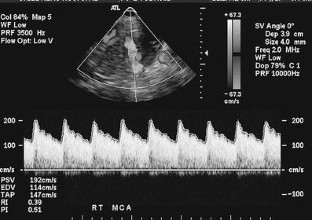

Fig. 1